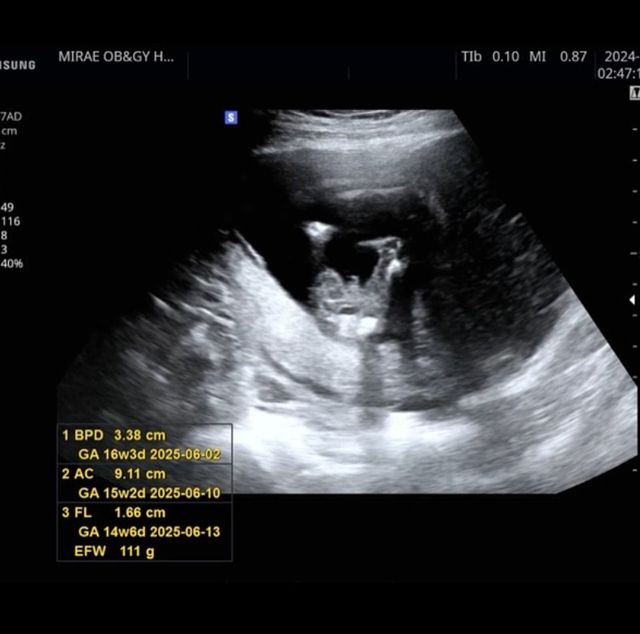

공개된 사진 속 전성초는 임신테스트기를 든 채 남편과 웃고있는 모습, 또한 초음파 사진을 공개해 시선을 모았다.